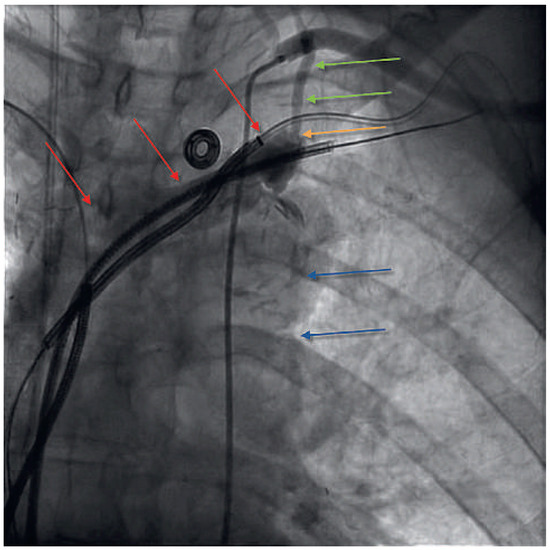

Anterior ST-Elevation Myocardial Infarction After Excimer Laser Extraction of Defibrillator Leads

by Reto Berli, Jürg Grünenfelder and Christophe Wyss

We describe a case of a so far unknown complication after failed extraction of defibrillator leads. Perforation of the LIMA bypass caused by Excimer laser created an arterio-venous fistula from the proximal bypass to the superior subclavian vein and occlusion of the distal [...] Read more.

We describe a case of a so far unknown complication after failed extraction of defibrillator leads. Perforation of the LIMA bypass caused by Excimer laser created an arterio-venous fistula from the proximal bypass to the superior subclavian vein and occlusion of the distal LIMA bypass with consecutive anterior S T-elevation myocardial infarction. Full article

Show Figures

Figure 1